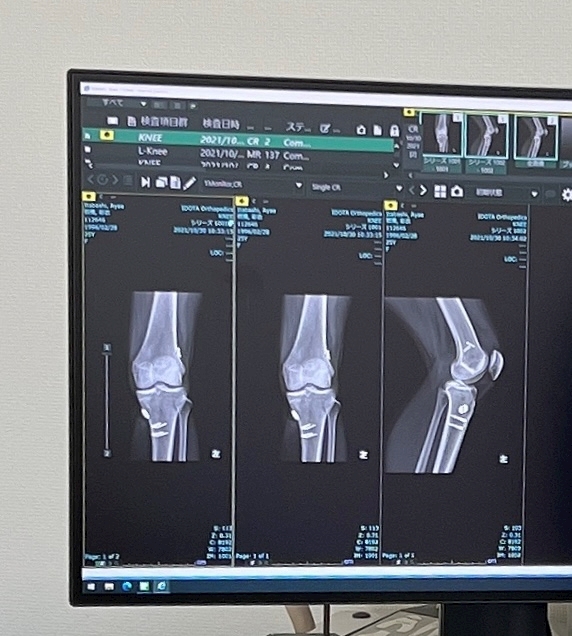

過去に2回、左膝の前十字靭帯を切っており手術してます。

右膝も、靭帯が緩んでいて、

下半身ガタガタです😢😢

1回目は器械体操

2回目はソフトバレー

ボルトが二本ずつ入ってる🔩

筋肉を移植して繋げてもらったのに

すーぐ無理して動くからすぐ悪くなる🥲🥊